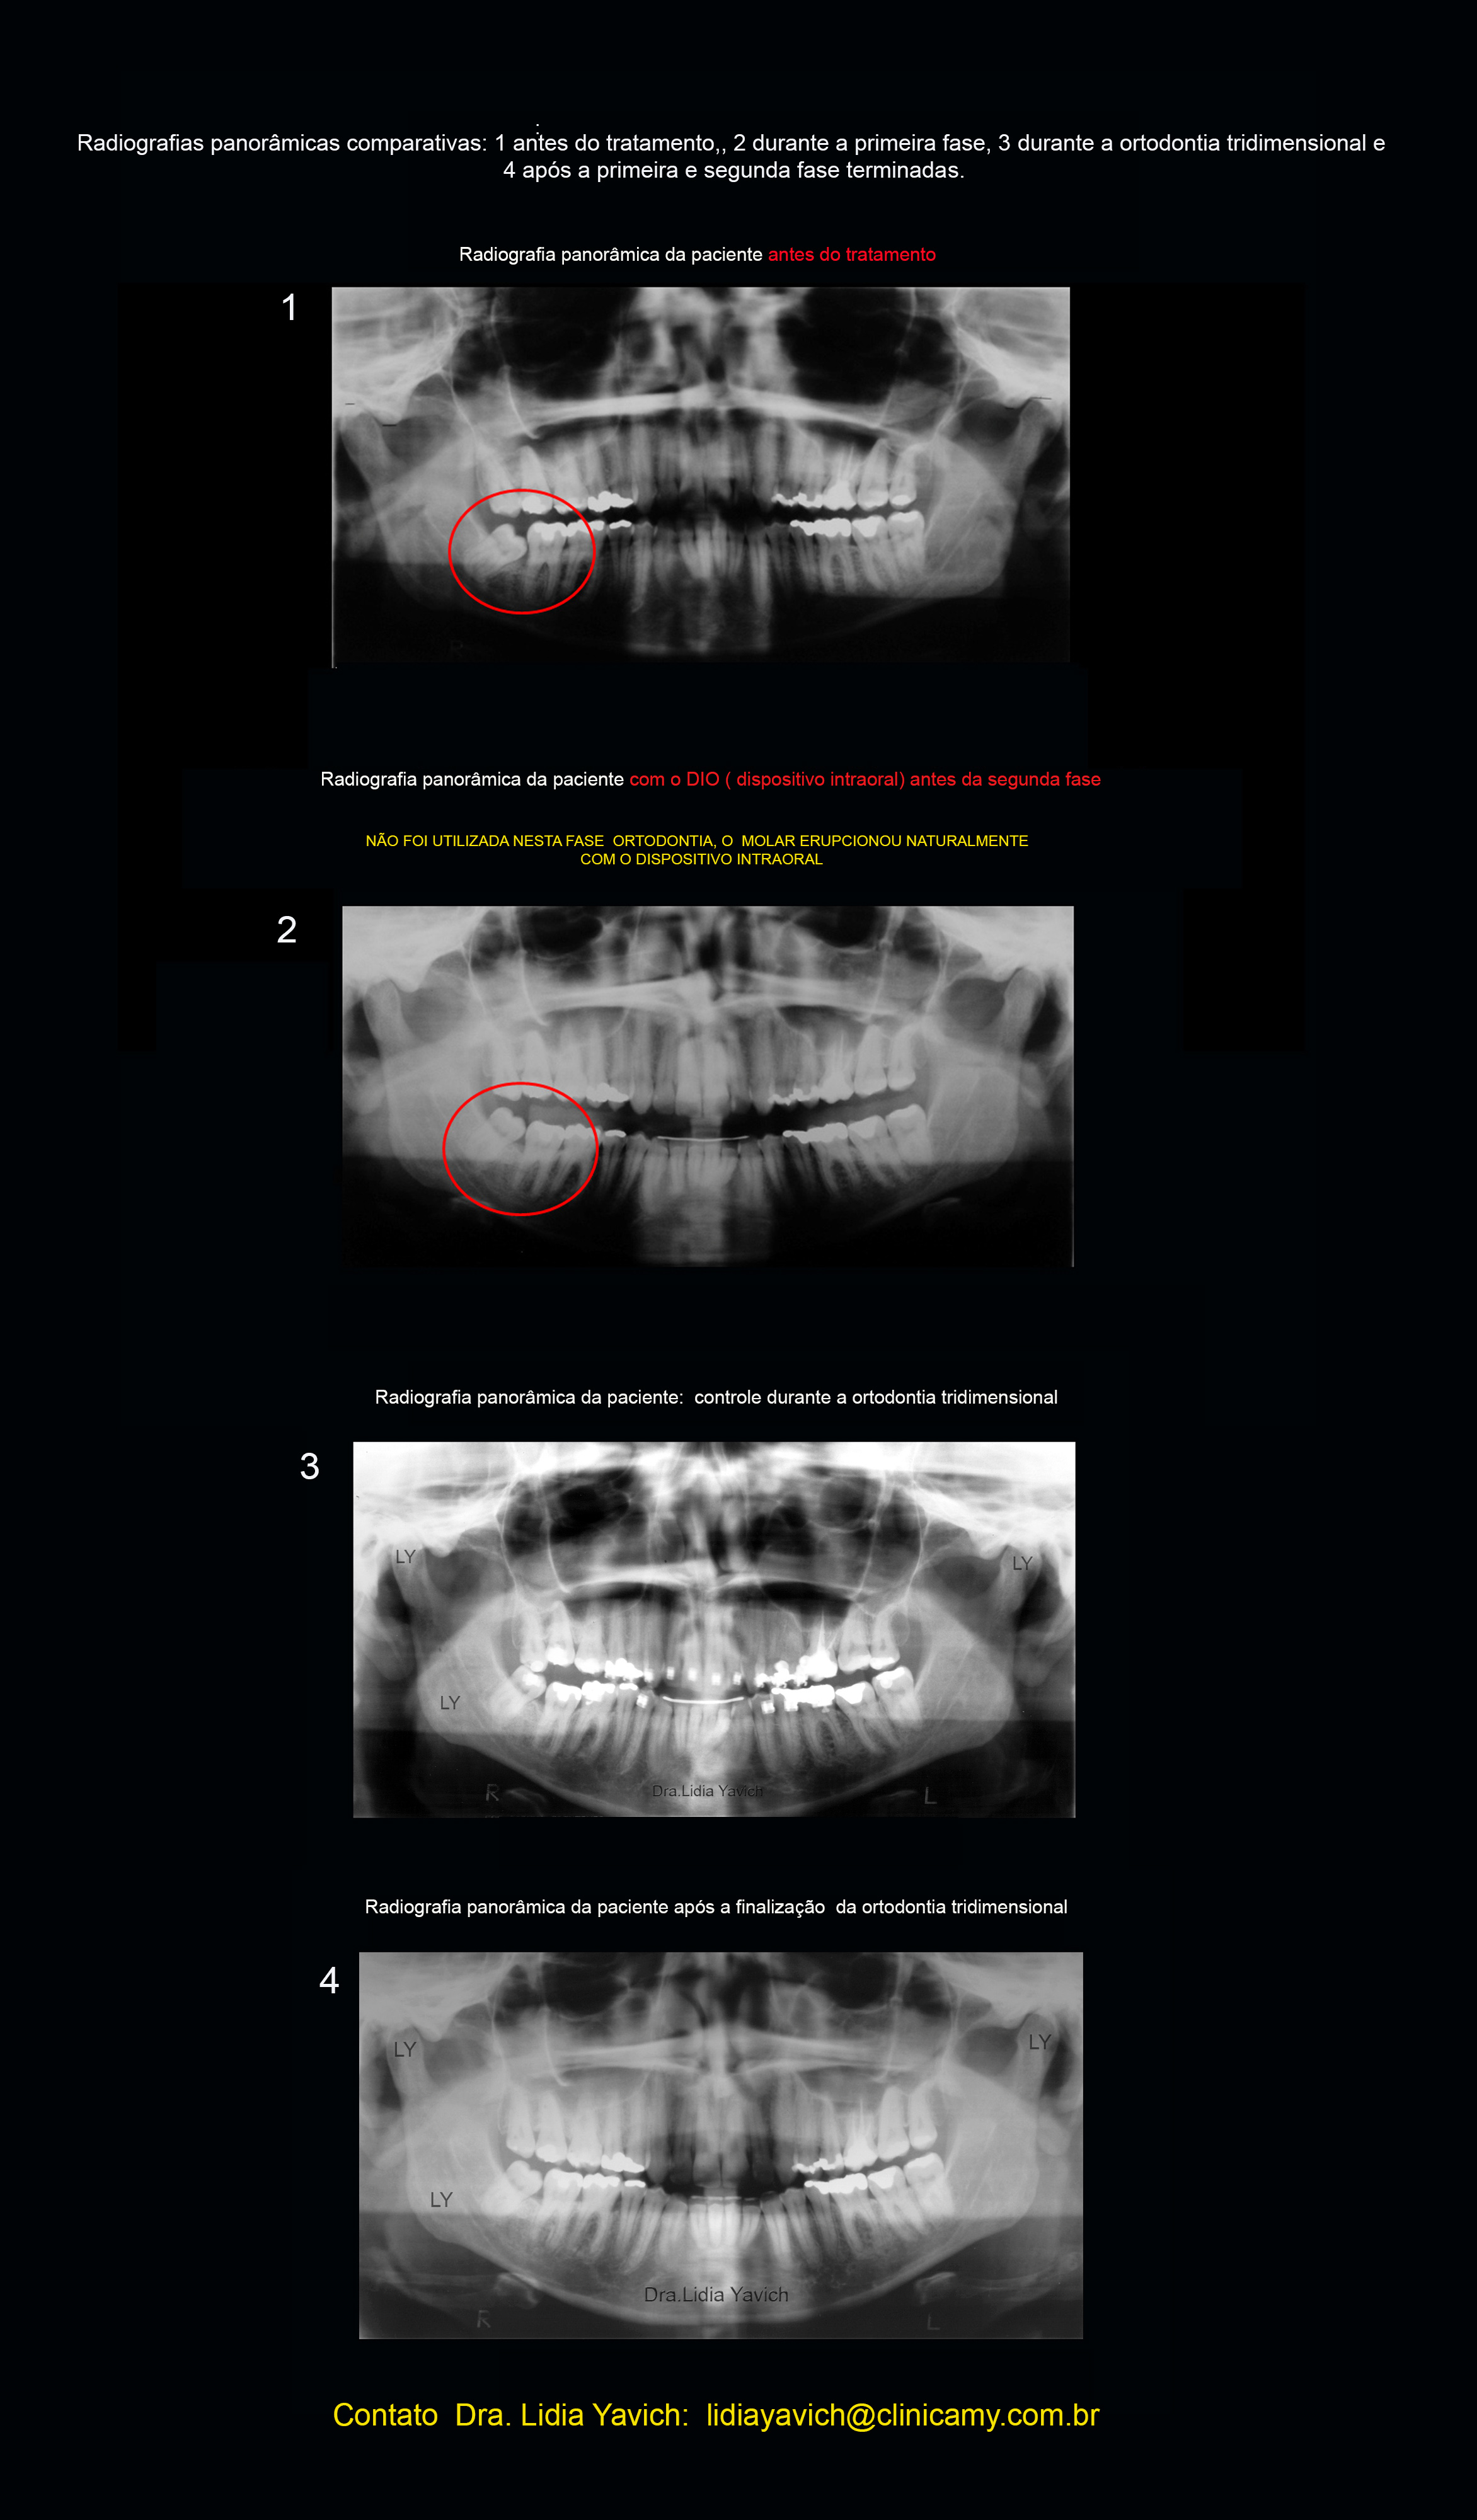

A radiografia panorâmica da paciente mostra os canais endodonticamente tratados no primeiro molar superior do lado esquerdo (26). O molar que a paciente relatou ter fraturado e tratado).

Nota-se o terceiro molar inferior do lado direito (48)encontra-se angulado, e impactado na distal do segundo molar inferior do lado direito.

No pedido da radiografia panorâmica antes de passar para segunda fase, neste caso (ortodontia tridimensional) pode se observar a erupção do terceiro molar inferior direito que estava impactado na distal do segundo molar inferior do lado direito. ( paciente de 31 anos de idade).

Nesta etapa só foi liberado o acrílico do DIO da região do terceiro impactado, devolvendo a dimensão vertical da paciente e permitindo a erupção da peça dentaria.

Comparação da radiografia panorâmica pré-tratamento e após a primeira fase com o DIO (dispositivo intraoral) instalado em posição neurofisiológica.

Radiografias panorâmicas da paciente comparativas: 1 antes do tratamento, 2 durante a primeira fase, 3 durante a ortodontia tridimensional, 4 após a finalização da ortodontia tridimensional.